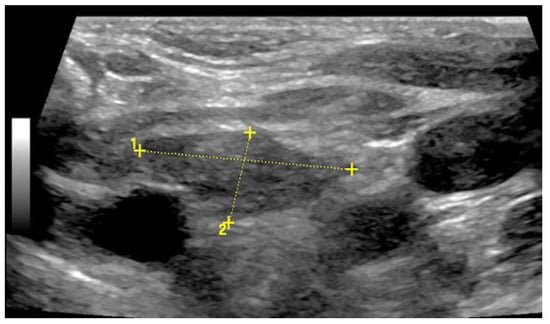

Fractures of ribs or the sternum can be diagnosed by visualizing an interruption of the cortical bone contour. Frequently, a step formation with a surrounding hematoma is found, which is visualized as a blurred-bounded, inhomogeneous, hypoechoic structure (Figure 4). Imaging of reparative processes and contusions is possible. In principle, traumatic fractures cannot be differentiated from pathological fractures unless a tumor soft tissue mantle can be visualized.

Figure 4.

Illustration of different patterns of traumatic rib fractures: (A) major step formation with hematoma (arrow); (B) minor step formation; (C) minimal contour disruption (arrow) with small hematoma; (D) small impression (arrow) with hematoma; and (E) long-standing fractures with bone consolidation.

Caution should be applied when diagnosing rib fractures in the region of the costochondral joint, because a small step is often found here that can look very similar to a fracture. The surrounding hematoma can help to differentiate a fracture from a costochondral joint. The diagnosis of sternal fractures is difficult on US, as cortical interruptions in the area of synchondrosis between the corpus and the manubrium sterni as well as incomplete fusions of the sternal bone spurs can also mimic fractures [10,11]. With knowledge of these synchondrosis a sternal fracture can be diagnosed with ultrasound much easier than with normal X-ray. It should be pointed out that in the case of rib fractures, the underlying structures should be visualized for confirmation or exclusion of associated injuries.